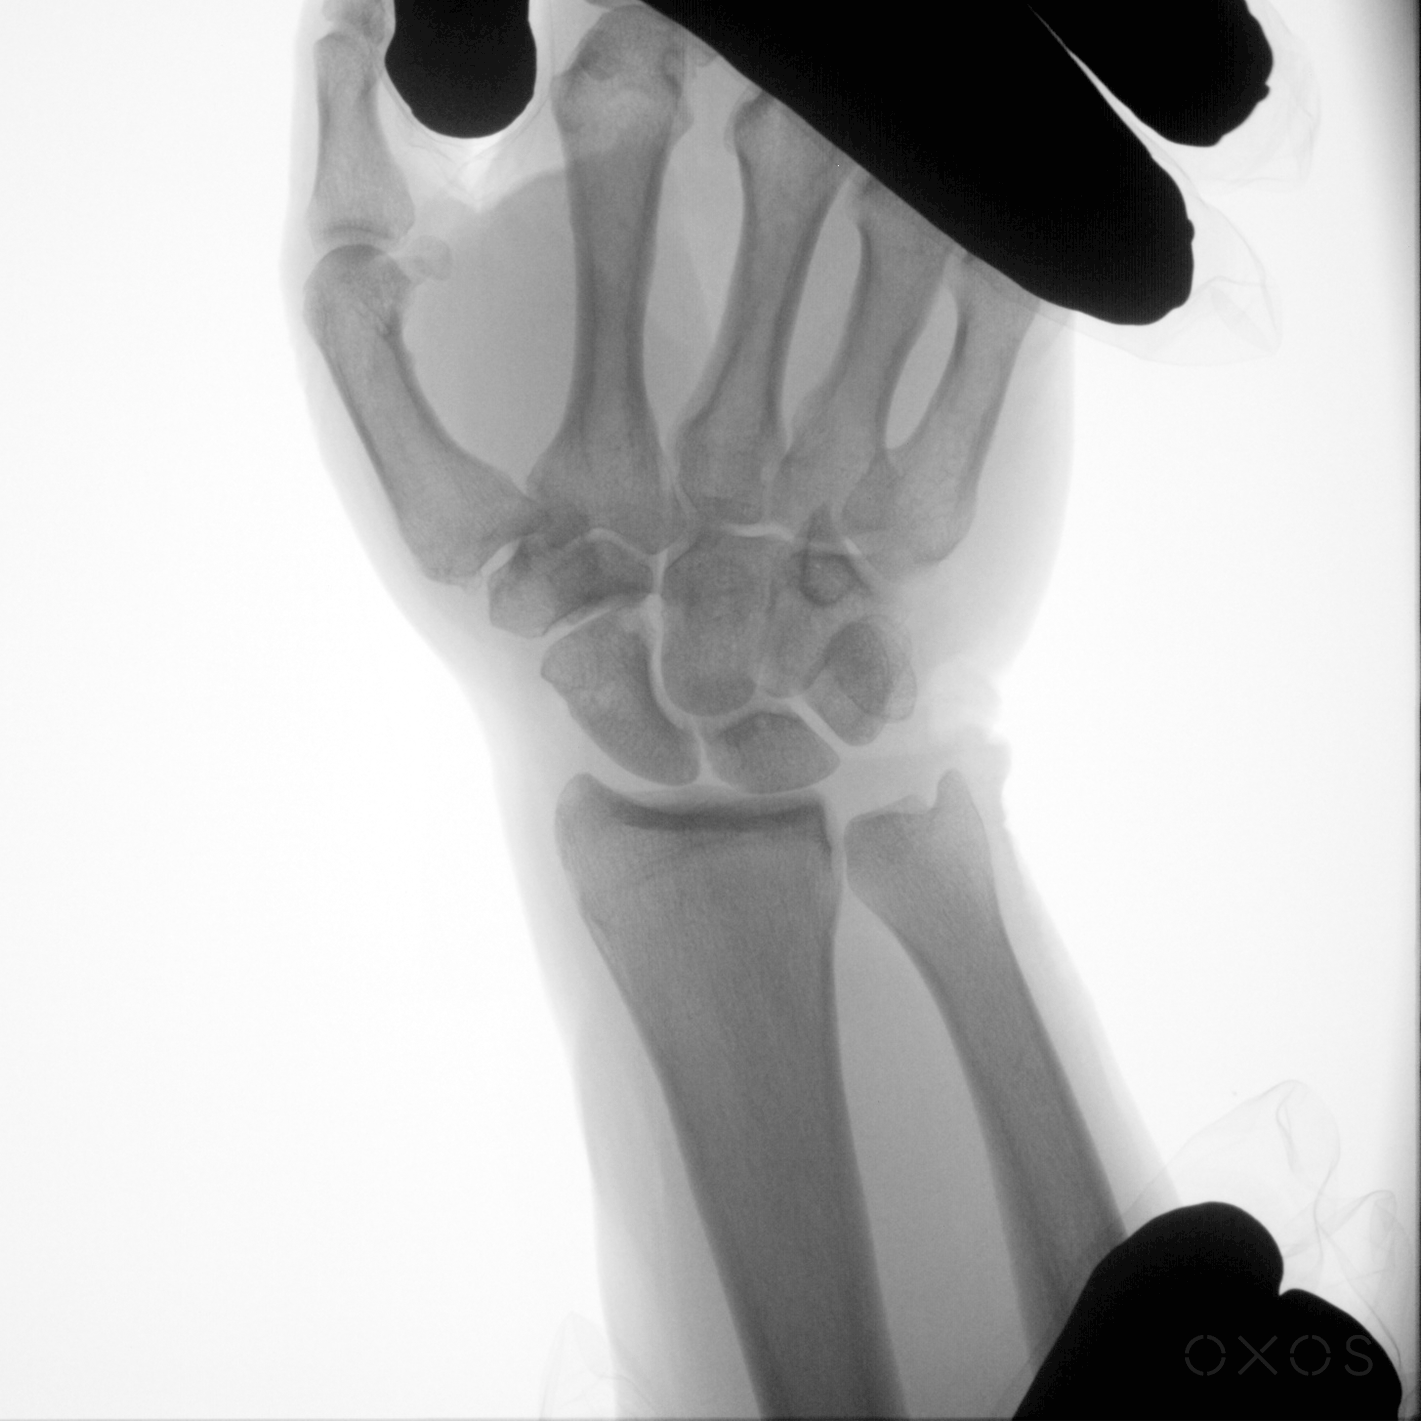

In orthopedic care, seeing anatomy in motion can reveal injuries, instabilities, and conditions that are hard to discern with static images. In this article, I’ll focus on a newer approach to medical imaging – Dynamic Digital Radiography, or DDR – that captures digital motion X-ray images, and I’ll offer examples of specific use cases where I prefer to use DDR over static radiography.

Dynamic Digital Radiography (DDR) is a powerful imaging technology that captures a series of high-quality X-ray images in sequence, creating a dynamic, motion playback view of anatomical motion. DDR compiles a series of images into a “cine loop“; this approach reveals unique insights into function and stability that can only be gleaned from seeing motion.

- Stress testing ligaments to assess laxity: DDR allows orthopedic surgeons to stress joints while imaging them dynamically, evaluating laxity and subtle instability that would not be visible in static views.

- Visualizing and assessing joint dislocations, relocations, and instability: Dislocation management typically requires multiple static X-rays before and after reductions. With DDR, I can view dislocation and relocation in motion with minimal radiation exposure.